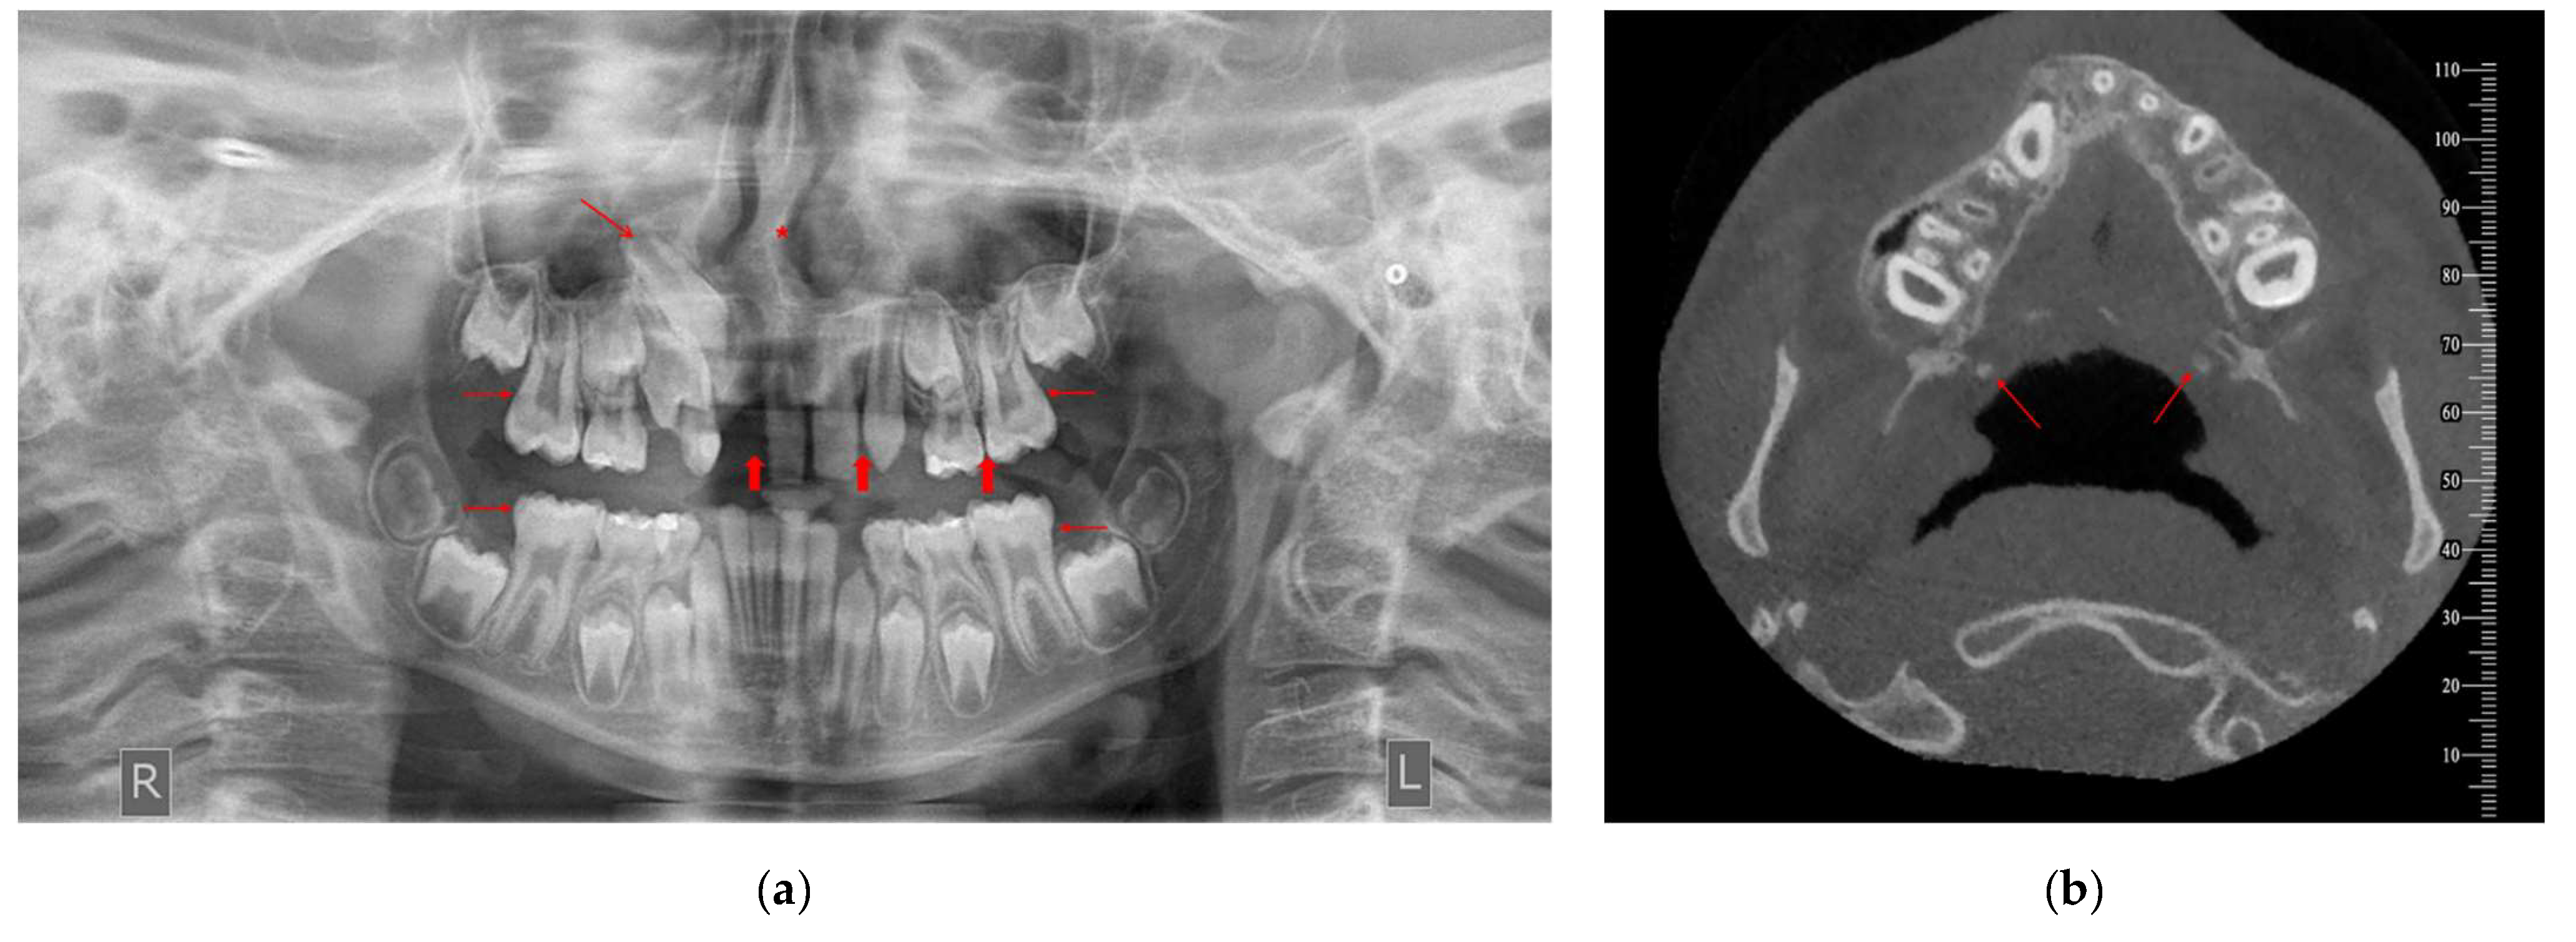

3.7. Temporomandibular Joint (TMJ) Abnormalities

The frequency of IFs in TMJ structures was significantly higher in the case group than in the control group (p = 0.003, Table 5). In the case group, 47.1% of the subjects had IFs in the TMJ region; in the control group, only 14.7% did. Nevertheless, it is worth mentioning that most participants in both groups (52.9% in cases and 85.3% in controls) did not present any TMJ abnormality (Table 5).

Temporomandibular joint abnormalities were observed at a high rate in the cleft and control groups in our analysis, with a rate of 47.1% and 14.7%, respectively. Santos et al. [14] did not detect any finding in the TMJ region of cleft patients, while studies on non-cleft populations found the rate of incidental TMJ findings at 4.3% [15] to 11.1% [20]. Four CBCT studies on non-cleft samples [15,20,21,23] detected a variety of abnormal findings (coronoid hyperplasia, condylar hyperplasia, condylar hypoplasia), physiological remodeling (flat condylar margins, subchondral sclerosis) and degenerative alterations (osteophytes, erosions) affecting the TMJ structures.

Figure 3. CBCT image of incidentally detected flat condylar margins bilaterally on TMJ of a male patient (10.7 years old) diagnosed with CP—UR. The findings are imaged in sagittal view [right (a) and left TMJ (c)], coronal view [right (b) and left TMJ (d)] and 3D reconstruction [right (e) and left TMJ (f)]. R: right, L: left.